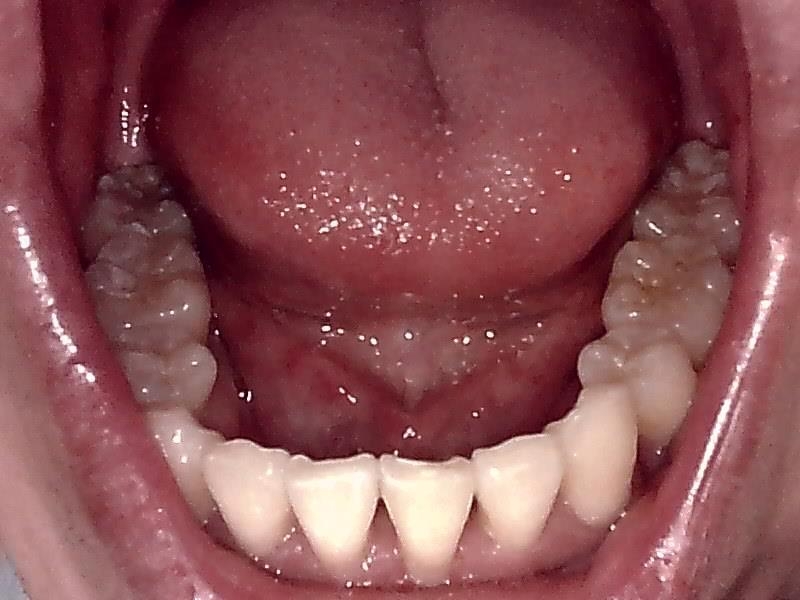

下顎咬合面観

下顎